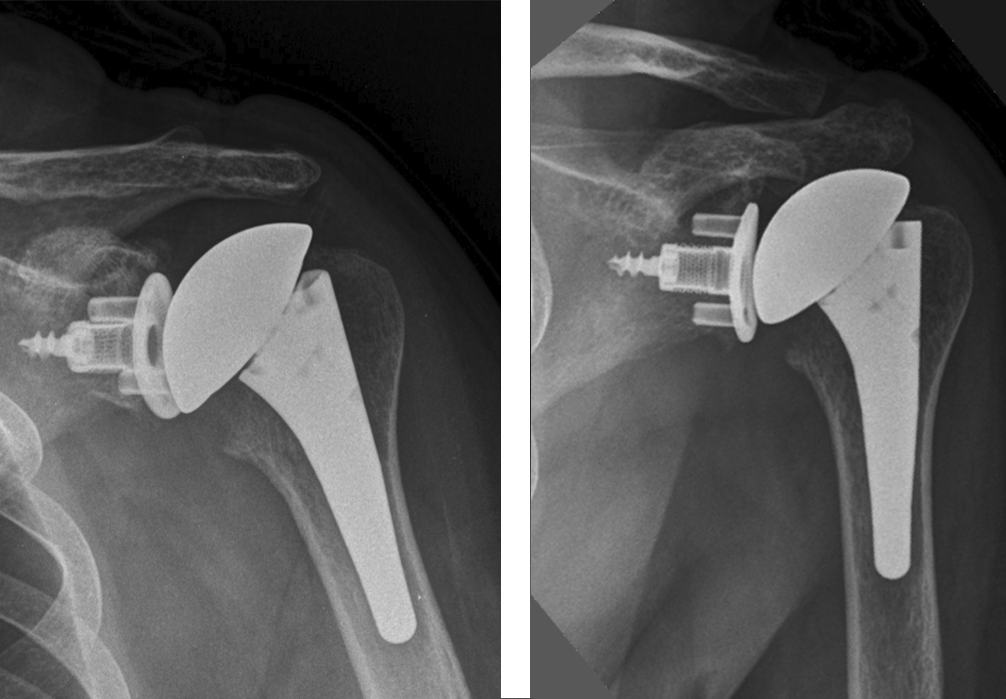

3 months post-op

Result:

- Very good clinical and functional evolution

- Very good ROM

- No pain